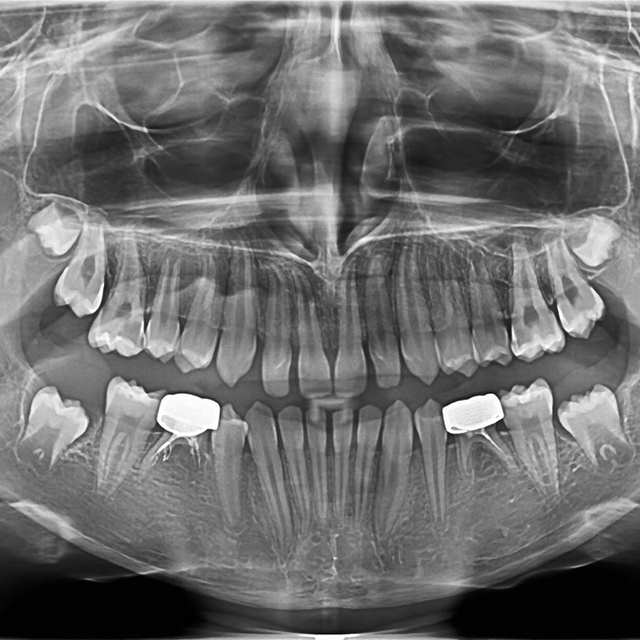

Dentistry, Trending Making a Permanent Difference with Zirconia Crowns (5-Year Follow Up) Ana Vinau, DDS

Dentistry, Health & Lifestyle, Trending My child needs pediatric dental crowns. What are my options? Sprig Oral Health Technologies, Inc.